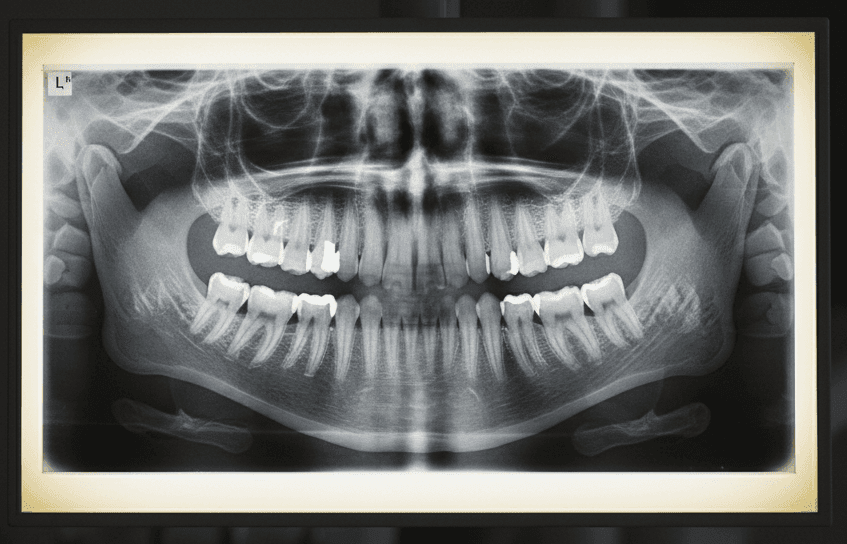

Кроме того, можно бесплатно пройти рентгенографические исследование. Детям дополнительно может бесплатно проводиться установка съемных ортодонтических конструкций для исправления прикуса, а также серебрение и реминерализация зубов.